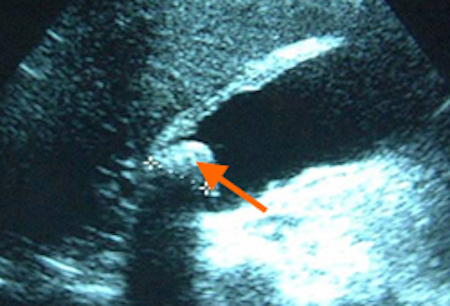

Cholelithiasis (gallstones)

Ultrasound of acute cholecystitis and presence of gallstones: the arrow points to a gallstone in the fundus of the gallbladder with its echogenic shadow below

Courtesy of Charles Bellows and W. Scott Helton; used with permission